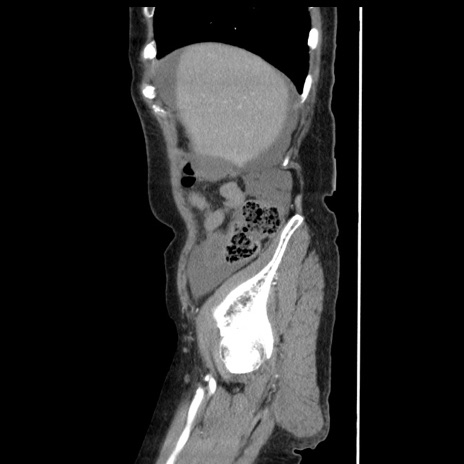

横断像